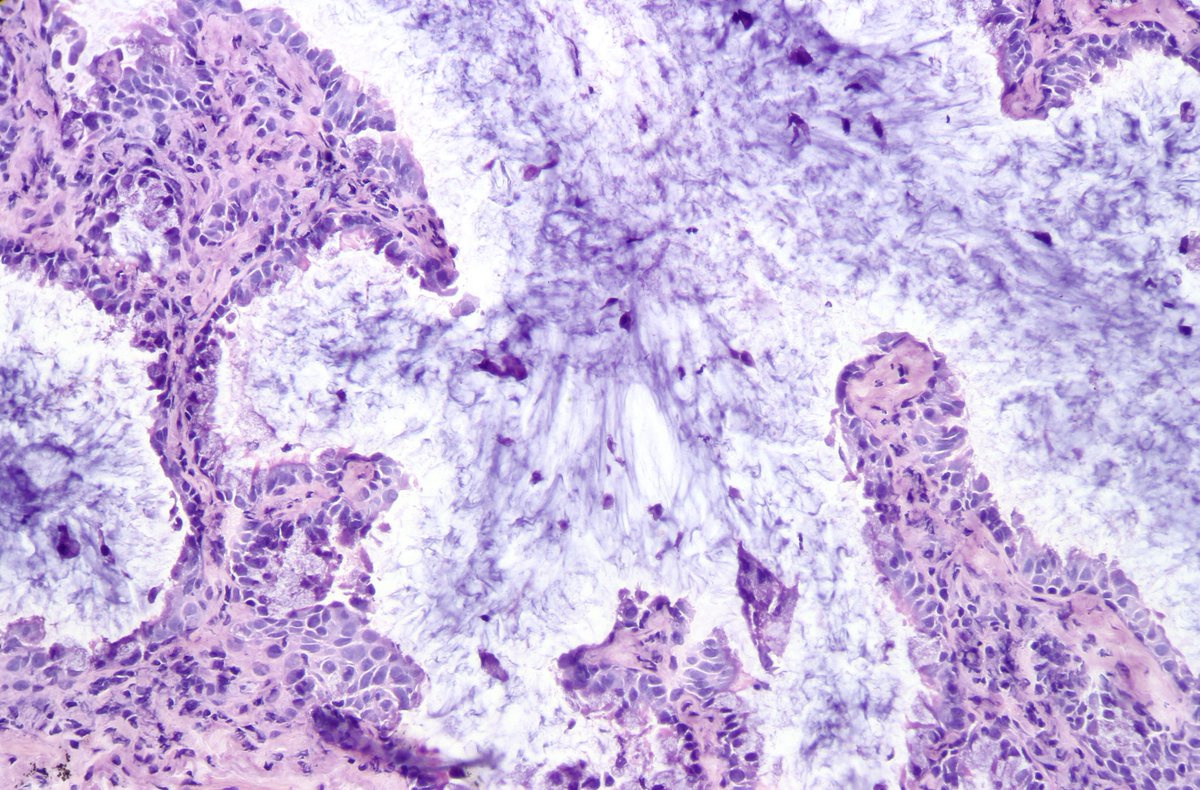

Atypical carcinoid of the lung exhibiting endobronchial growth, increased mitotic activity was seen (2-10 per 10 HPF). #pathology #PulmPath